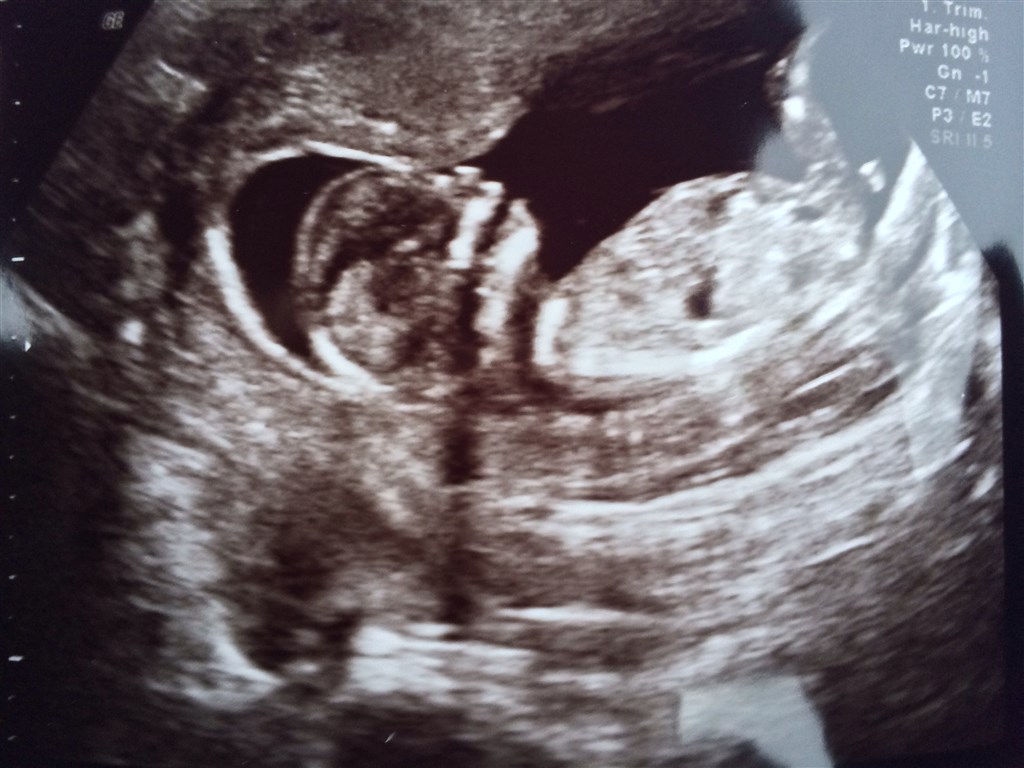

Vi har idag været til NF scanning og set en helt perfekt lille sprællebasse! Den lå og vinkede og fik også lige en tår fostervand.

Det var så vildt at opleve, og nu bliver det hele pludselig mere virkeligt! Det er jo en lille miniature baby jeg har i maven!!

Vi fik en meget lav risikovurdering på 1:<20.000 og alt så normalt og fint ud.

Blev desuden rykket 3 dage frem, så termin hedder nu 4/6.